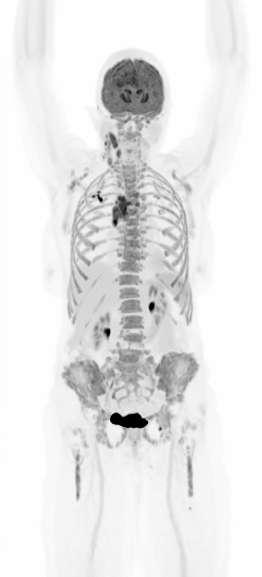

18 The Whole Picture: Total-Body PET and the Future of Biopharma

Advanced PET technology can deliver full-body scans in minutes, opening exciting new avenues for research and discovery. Dr. Juliana Maynard and Dr. Ian Wilson of Medicines Discovery Catapult explore how the UK’s National PET Imaging Platform can expand its potential impact through global data sharing and continued innovation.

The Whole Picture: Total-Body PET and the Future of Biopharma

What if a clinical scan could transform biopharmaceutical innovation and patient care, streamlining drug development, clinical trials, and complex disease diagnosis? Total-body Positron Emission Tomography (PET) imaging is turning that vision into reality, offering a full-body, real-time view of human physiology.

Total-body PET is redefining what is possible in molecular imaging and biopharmaceutical development. This advanced PET technology can deliver full-body scans in minutes, with a sensitivity of up to 40x greater than conventional standard field PET scanners1 and potential for significantly lower radiation exposure. This opens exciting new avenues for research and discovery. It enables clinicians to study disease in real time across the whole body, revolutionising how we diagnose, stage and treat complex conditions like cancer, cardiovascular disease and neurodegenerative disorders. For patients, this means faster scans and earlier interventions, with the opportunity for more personalised treatments. For research and industry, it unlocks a powerful new platform for evaluating novel therapies, tracking their behaviour and accelerating their path to market.

But realising the full potential of total-body PET requires more than cutting-edge scanners. It demands a robust infrastructure, one that includes a reliable supply of radiotracers and an integrated framework for data sharing and collaboration. In the UK, the National PET Imaging Platform (NPIP) is building exactly that. What it reveals is not just a clearer image of the body, but a blueprint for the future of biopharmaceutical development.

PET scanning involves the injection of radiotracers into the body. Radiotracers are made up of two parts: a radionuclide (a compound or molecule that emits radiation), combined with a molecule or drug that guides the radionuclide to a specific area of the body to be studied or targeted for treatment. As the radionuclide decays, it will emit gamma rays inside the body, which are detected by the PET scanner. Through image processing, the detected gamma rays are used to build a detailed picture of where the radiotracer has accumulated. This picture helps clinicians and researchers to diagnose diseases and make decisions about treatments.

Continued technological advances in hardware and software have led to a new generation of PET scanners with far greater sensitivity and resolution. While conventional PET relies on multiple bed positions and generating multiple images to acquire

a whole picture of the body, total-body PET has a field of view wide enough to take an image from head to toe in a single scan, and a detector capable of 40x higher sensitivity.¹ This means the whole body can be imaged faster, at higher resolution and in real-time. It also means lower doses of radiotracer are required to generate the same amount of detail (Table 1).1,3

Feature

Conventional PET Total-Body PET

Large Axial Field of View (LAFOV) 15–20cm >100cm*

Sensitivity Moderate Ultra-high (up to 40x higher for whole-body images)

Average Total-Body scan time** 10–30 min 30 seconds–3 minutes

Average radiation dose for a full-body scan** ~370 MBq ~9.25 MBq

Dynamic imaging potential (continuous capture of data over time)

Patient throughput

Tracers can be followed for ~3 half-lives, limiting dynamic imaging

Lower

Tracers can be followed for 5–6 additional half-lives, enabling whole-body, real-time imaging

Potential for twice as many clinical scans per day

*Scanners in the NPIP network have a LAFOV of between 106–194cm. **Based on (18F)-FDG scan procedures.

Table 1. Differences between conventional PET scanners and total-body PET scanners.1,4,5,6

Importantly, total-body PET does not replace conventional PET imaging. Conventional PET remains indispensable in clinical practice, especially when imaging needs are localised to a specific area of the body. But for complex diseases that span multiple organ systems or in cases where lower doses of radiation are required, total-body PET offers a transformative new lens:

• In oncology, total-body PET enables earlier detection of metastases and monitoring of tumours throughout the body, as well as increasing the potential for radiotheranostics (radiopharmaceuticals that can both detect and treat disease).7,8

• In cardiology, it helps us to understand how heart disease affects, or is affected by, other organ systems, supporting approaches to systems-based or preventative cardiovascular medicines.9

• In neurology, it allows the brain to be imaged at the same time as the rest of the body, which is critical for our understanding of complex neurodegenerative diseases.10

• In infectious disease and immunology, it offers a powerful tool for visualising infection and immune responses throughout the body, opening new avenues for treatment.11

• Finally, the higher sensitivity of total-body PET reduces the amount of radiotracer required for a high-resolution image, enabling paediatric studies in children and other patient populations where higher levels could be unsafe.12

In short, total-body PET is paving the way for a future where a systems-level understanding of human physiology may be possible. This will enable new insights into complex disease mechanisms and therapeutic targets where whole-body context is essential, or where study was previously difficult.